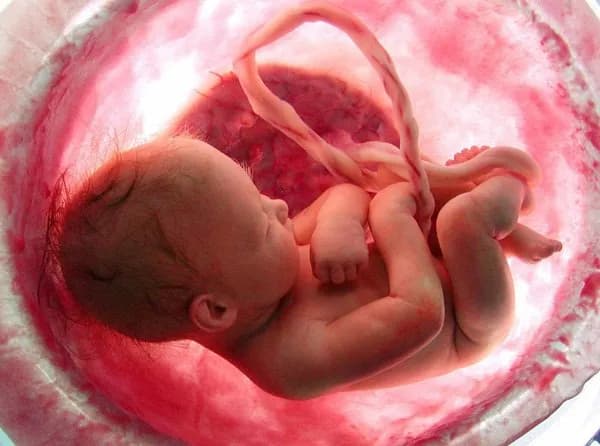

Tìm hiểu hội chứng thiểu sản thất trái ở thai nhi

Hội chứng tim trái giảm sản (HLHS): Dị tật tim bẩm sinh cần được phát hiện và điều trị sớm

Hội chứng tim trái giảm sản (...